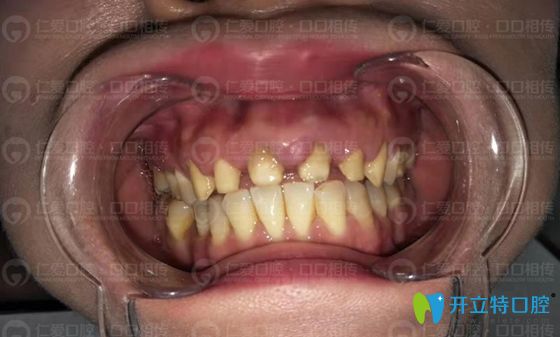

<!--<i data=20240703-sp></i>-->口腔對烤瓷牙失敗的修復(fù)效果

上周,劉先生帶女兒來咨詢牙齒矯正時(shí),表示對李明醫(yī)生新做的全瓷牙冠非常滿意!